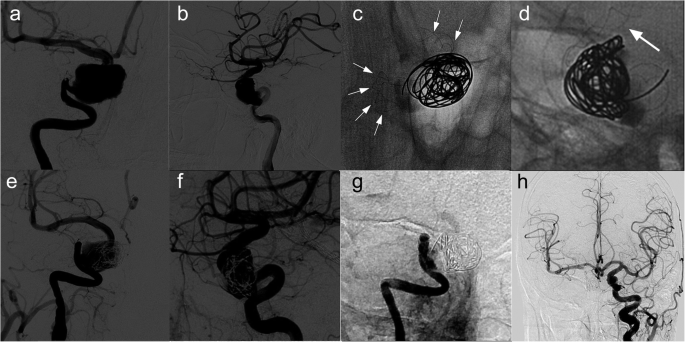

We selected the final digital subtraction angiographic follow-up image for each patient as the time point to evaluate the efficacy of TFD placement. Angiographic follow-up data were obtained for all seven patients (Table 2), with a median imaging follow-up period of 57.5 ± 16.7 (range, 6–69) months. All seven patients obtained favorable angiographic follow-up results (five patients’ O’Kelly–Marotta Scale grades were D (Figs. 1 and 2), and two patients were grade C). In one of the seven patients, (Fig. 3), parent artery occlusion was seen in the 6-month digital subtraction angiographic image. The occlusion was located in the TFD, but there was no clinical manifestation associated with cerebral infarction because the left internal carotid artery provided sufficient blood for the right anterior circulation through the anterior communicating artery.

Images from a patient with a left large cavernous carotid artery aneurysm (patient 1). a–c Preoperative angiograms of the left internal carotid artery showing a large cavernous carotid artery aneurysm. d Immediately postoperative angiogram of the left internal artery showing reconstruction of the parent vessel and contrast stasis in the lumen of the aneurysm. MRI 4 months posttreatment (f) compared with the 2-day posttreatment MRI (e) showing a slight reduction of the aneurysm size (white arrow) and increased space around the brainstem. g, h Angiogram 66 months posttreatment showing the occluded aneurysm and reconstruction of the left internal carotid artery. MRI, magnetic resonance image

Images from a patient with a left large cavernous carotid artery aneurysm (patient 1). a–c Preoperative angiograms of the left internal carotid artery showing a large cavernous carotid artery aneurysm measuring 20.6 × 16.6 mm. d Immediately postoperative angiogram of the left internal artery showing reconstruction of the parent vessel and contrast stasis in the lumen of the aneurysm. e, f Angiograms 66 months posttreatment showing the occluded aneurysm and reconstruction of the left internal carotid artery. g, h Unsubtracted view of 66 months posttreatment confirming that the stent was in good shape with no compression